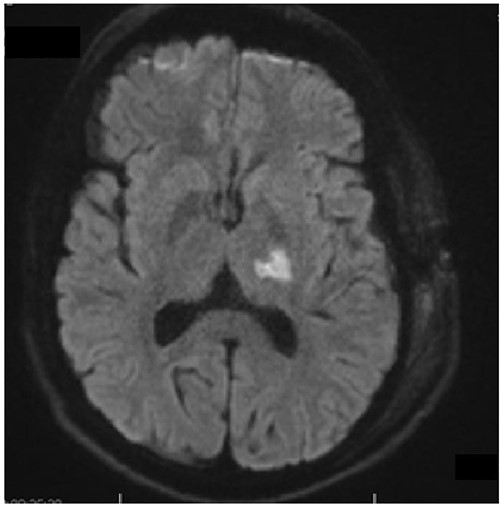

In regard to the new neurological manifestation we performed a brain magnetic resonance imaging (MRI). This demonstrated in the diffusion-weighted imaging (DW-MRI) an ischemic area in the posterior limb of capsula interna and a ring-shaped lesion in the thalamus, showing in Fig. 2. Moreover it appeared a contrast agent enhancement of 5-mm temporal, which was evaluated as a sing of residual tumor. During the inpatient stay we initiated physiotherapy and ergotherapy, which both resulted to a gradually improvement in clinical performance. In the meantime the histological finding revealed a pilocytic astrocytoma, WHO grad I.

Axial diffusion-weighted MRI shows restricted diffusion in the posterior limb of internal capsule.